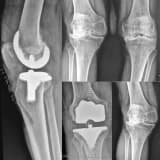

OSTEOPOROZA ( KEMİK ERİMESİ) BAĞLI KALÇA KIRIKLARI

Yaşlılardaki kalça kırıkları yaşam süresinin artması ile birlikte oldukça çok gördüğümüz bir sağlık sorunu haline gelmiştir. Kemik erimesi bulunan yaşlılarda boy mesafesinden basit düşmelerle bu kırıklar meydana gelebilmektedir. Kalça kırıklarının tedavisi cerrahidir. Tedavinin amacı hastalara tekrar ağrısız bir kalça eklemi kazandırmak, kırık öncesi günlük aktivitelere bir an önce dönüşü sağlamaktır. Eğer varsa eşlik eden kronik hastalıklar ameliyat öncesi ilgili branşlarla konsültasyonlar yapılarak gerekli hazırlıklar tamamlanmalı ve mümkünse ilk 72 saatte operasyon gerçekleştirilmelidir.